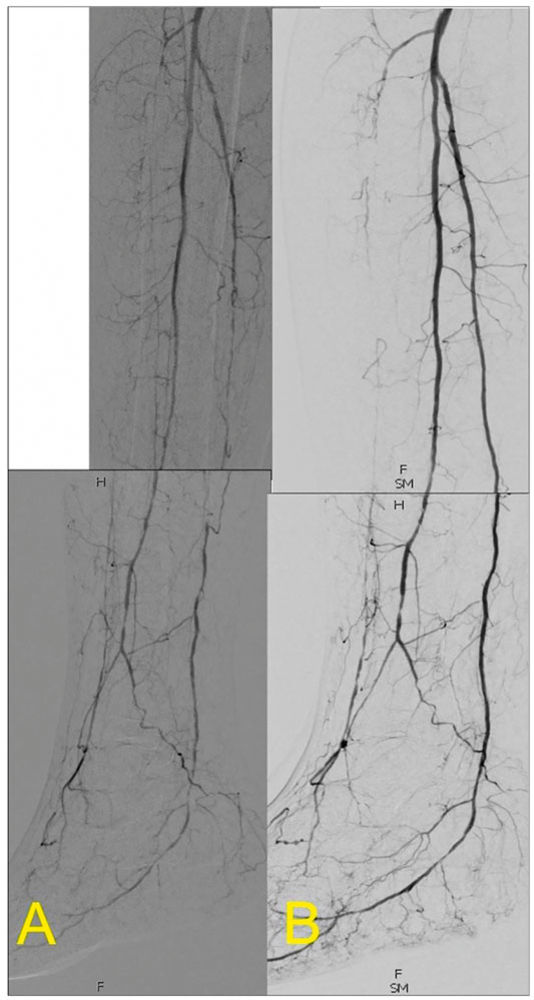

Adäquate Wundbehandlung, antibiotische Therapie bei klinischen Zeichen der Infektion und konsequente Druckentlastung gemäß spezifischer Empfehlungen zum diabetischen Fuß sind obligat [11]. Bei Vorliegen einer CLTI besteht, im Gegensatz zur Claudicatio intermittens, die absolute Indikation zur Revaskularisation mit dem Ziel der Wundheilung und mittelbar des Extremitätenerhalts bzw. der Amputationsvermeidung [1]. Revaskularisierende Maßnahmen sollten interdisziplinär diskutiert werden, da aufgrund der komplexen Datenlage keine generelle Empfehlung für eine „bypass first“ oder „endovascular first“-Strategie bei CLTI möglich ist. Die BEST-CLI-Studie (2022) zeigte bei weit über 1.000 Patienten mit CLTI und infrainguinaler Bypasschirurgie eine reduzierte Rate an extremitätenbezogenen Ereignissen/Tod (42,6 Prozent) gegenüber endovaskulär behandelten Patienten (57,4 Prozent) dann, wenn ein Segment der V. saphena magna als Material für die Bypasschirurgie tauglich war [12]. Hingegen zeigte die kleinere, überwiegend in Großbritannien durchgeführte BASIL-2-Studie (2023) an Patienten mit CLTI und Erfordernis zur Revaskularisation der Unterschenkelarterien (und gegebenenfalls proximaler Arterien) eine höhere Rate an amputationsfreiem Überleben nach endovaskulärer Therapie vs. Bypasschirurgie (47 Prozent vs. 37 Prozent), allerdings bei einer höheren Rate an Re-Interventionen [13]. Bei isolierten Unterschenkelarterienobstruktionen wird meist eine primäre endovaskuläre Strategie konsentiert, so auch im aktuellen Fall (Abbildung 3). Die SWEDEPAD-1-Studie konnte jedoch auch bei CLTI-Patienten keinen Nutzen von drug-eluting-Technologien hinsichtlich einer Reduktion der Amputationsrate zeigen [14]. Für Fälle, bei denen mangels pedaler Zielgefäße eine Revaskularisation nicht sinnvoll möglich ist, steht mit der katheterbasierten Arterialisierung tiefer Venen ein Alternativverfahren mit potenziellem Nutzen in Kohortenstudien zur Verfügung [15], welches seitens des G-BA einer Nutzenbewertung unterzogen wird.

Abbildung 3: Rekanalisation der A. tibialis posterior mittels PTA, mit Wiederherstellung eines ungehinderten Blutflusses zum Fuß.